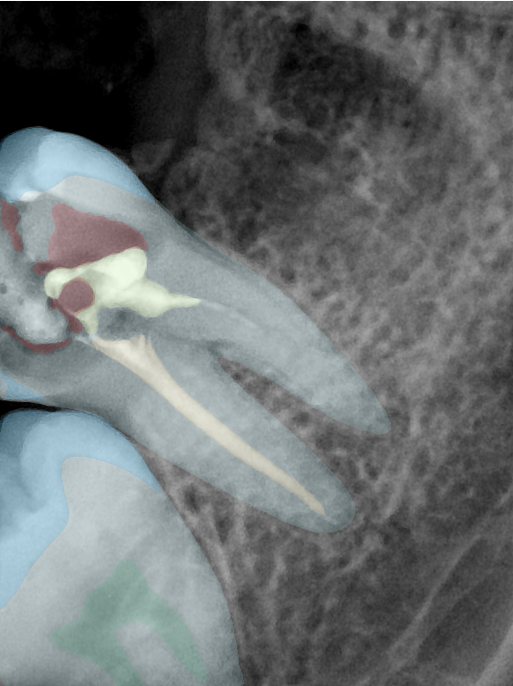

CR/DR 牙齿分割阶段记录

当前进展

- 完成了 CR/DR 牙齿相关分割训练

- 当前结果已经达到阶段预期,但仍有细节问题需要继续处理

相关测试

遇到的问题

- 训练过程中出现过 mask 下移问题

- 部分结果会出现 box 填充异常

- mask 边缘仍然有比较明显的锯齿感

参考

第二版算法问题测试